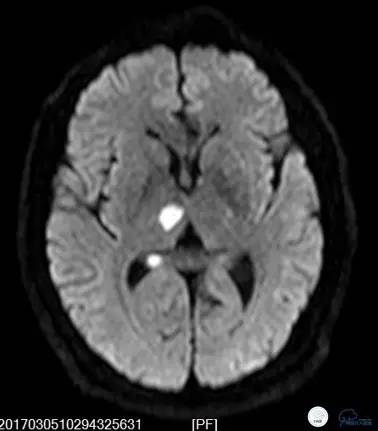

就诊于外院查头颅核磁DWI+MRA(图1-2):中脑右侧及右侧丘脑新鲜脑梗死,椎基底动脉及双侧大脑后动脉未见显影。住院予波立维、拜阿司匹林抗血小板聚集、立普妥降脂治疗后症状无好转,病情逐渐加重。为进一步行血管内治疗来我院。

图1

图2